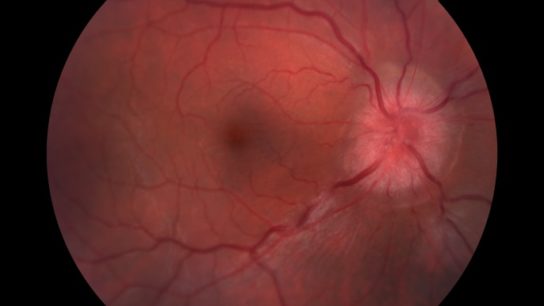

A study identifies alterations in binocular vision among patients with multiple sclerosis.

Those treated with phenytoin saw a 30% reduction in retinal nerve fiber loss.